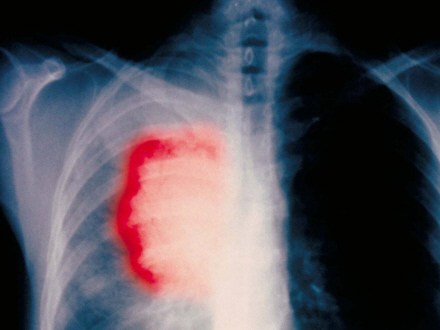

Flere kvinder får lungekræft

SUNDHED & SYGDOM: Læger advarer om, at et stigende antal kvinder får konstateret lungekræft.

Omfanget af kvinder, der får lungekræft, vokser så hastigt, at det ligner en epidemi, advarer lægerne.

Stigningen er på mellem fire og fem procent om året, og det er decideret foruroligende, siger eksperterne.

Der bliver hvert år konstateret 28.000 nye tilfælde af lungekræft i Spanien. Og for første gang har sundhedsmyndighederne også netop fastslået, at der i Barcelona for første gang nu er flere kvinder, der dør af lungekræft end af brystkræft.